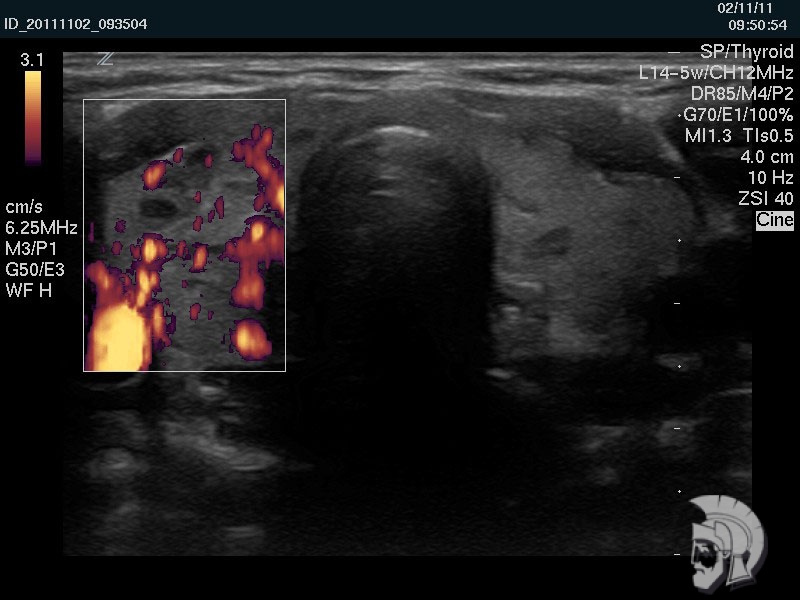

Фото щитовидной железы. Тот же случай. При исследовании в режиме энергетического допплера в правой доле щитовидной железы определяется выраженное усиление кровотока |

УЗИ щитовидной железы позволяет изучить структуру самой щитовидной железы и регионарных лимфатических узлов, определить размеры и объем щитовидной железы, особенности кровоснабжения в режимах энергетического ДОППЛЕРа и цветового допплера.

Использование ультразвуковых аппаратов экспертного класса с режимами энергетического допплера и цветового допплера позволяет врачам Курортной клиники мужского здоровья выявить патологические изменения щитовидной железы на ранних этапах.